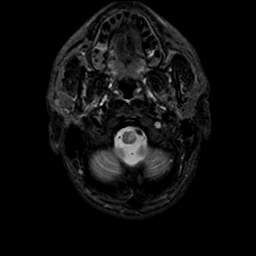

MR Study #9, April 14, 1991 -- Slice #3

[Home][Help][Clinical][Tour 1][Tour 2] Slice 3